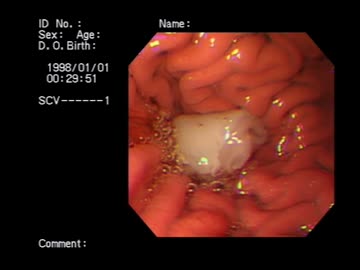

【丸呑み】胃で食べ物が消化される様子を観察してみた〜生ハム〜【vore】